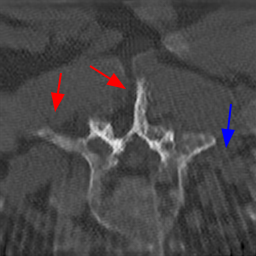

Disentanglement and explicit shape constraints. As shown in Fig. 4, we can see streak metal artifacts nearly everywhere in . M1 can roughly disentangle artifacts and anatomical information but strong vertical artifacts and strange air area appear in (see red arrows of M1 in Fig. 4). For the anatomical structure, M1 learns to segment vertebrae with fully supervised and applied on various CT images, but fails to suppress the false bony structure in and as may misclassify some metal artifacts as bone.

Implicit shape constraints. With , all segmentations are improved with higher Dices and smaller ASDs, see Table 1. As shown in Fig. 4, , and become similar but the high density bone is not correctly segmented in as it maybe treated as metal artifacts. Comparing between M2 and M1, the abnormal air region disappears but metal artifact reduction performance is still not satisfactory.

Anatomy-aware generation. With AADE layer in M3, , and are substantially improved as shown in Table 1. Note, is used as attention map, so we do not expect it to be identical to . In , metal artifacts are further suppressed comparing with M2. Thus, AADE is critical to our anatomy-aware artifact disentanglement framework. With the special structure, can be punished in the image translation and reconstruction processes and the other encoders and generators receive more guidance. However, as shown by blue arrows in Fig. 4, we observe a shadow of vertebra edge of appears in of M3 and the vertebra boundaries get smoothed out in . It may be because sharp edges are encoded as metal artifacts and forced to be added to by artifact consistency loss .

Removal of . To mitigate vertebrae shadows, we remove . The segmentation performance of most images in M4 gets improved because of better synthetic images. Overall, in M4 yields the best segmentation performance for CBCT images with an average Dice of 0.847 and an average ASD of 1.54 mm. For the synthetic images, M4 generates with the best quality and least metal artifacts among all the models. M4 also outputs without vertebra shadows. The results indicate our shape-aware network could preserve anatomical details and transfer the metal artifacts precisely without .